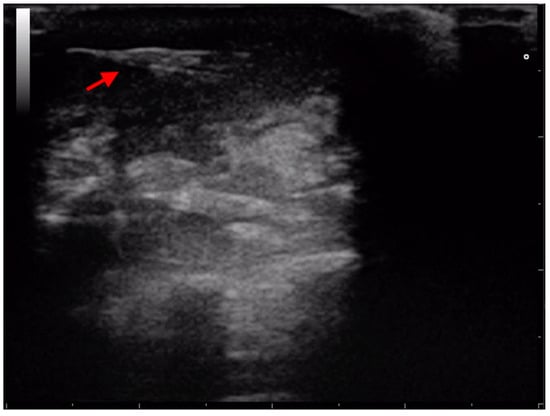

- Gnudi, G.; Volta, A.; Bonazzi, M.; Gazzola, M.; Bertoni, G. Ultrasonographic features of grass awn migration in the dog. Vet. Radiol. Ultrasound 2005, 46, 423–426. [Google Scholar] [CrossRef]

- Della Santa, D.; Rossi, F.; Carlucci, F.; Vignoli, M.; Kircher, P. Ultrasound-guided retrieval of plant awns. Vet. Radiol. Ultrasound 2008, 49, 484–486. [Google Scholar] [CrossRef] [PubMed]

- Fauchon, E.; Lassaigne, C.; Ragetly, G.; Gomes, E. Ultrasound-guided removal of vegetal foreign bodies in the lower extremities of dogs: A retrospective study of 19 cases. Vlaams Diergeneeskd. Tijdschr. 2017, 86, 285–290. [Google Scholar] [CrossRef]

- Manfredi, S.; Covi, G.; Bonazzi, M.; Gnudi, G.; Fumeo, M.; Miduri, F.; Daga, E.; Volta, A. Ultrasound-guided removal of soft tissue foreign bodies in companion animals: A case series. Vet. Med. 2020, 65, 49–55. [Google Scholar] [CrossRef]